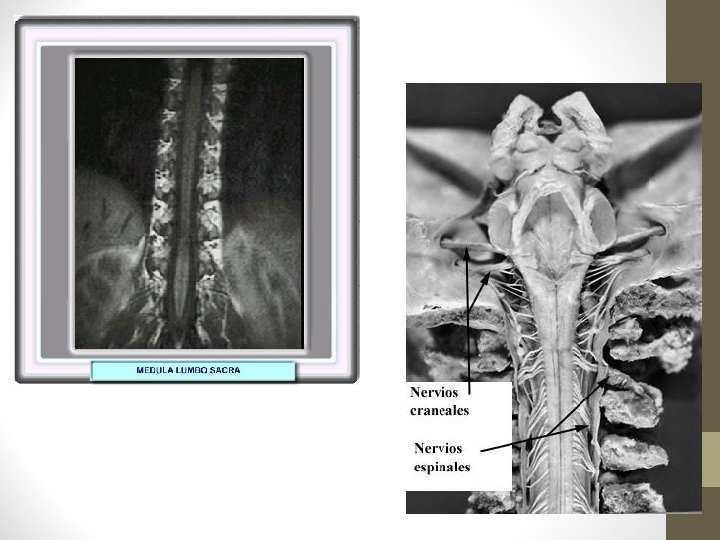

MÉDULA ESPINAL REGIÓN ESTRUCTURA ANATÓMICA FORMA CERVICAL 8 segmentos cervicales: intumescencia cervical (C 3 a T 2) Ovalada TORÁXICA 12 segmentos toráxicos Redondeada LUMBAR 5 segmentos lumbares; intumescencia lumbar (L 1 a S 3) Redondeada a ovalada SACRA 5 segmentos sacros; cono medular Redondeada COCCÍGEA 1 segmento coccígeo; filum terminal Filamentosa

Nervios Raquídeos o Espinales: 31 pares